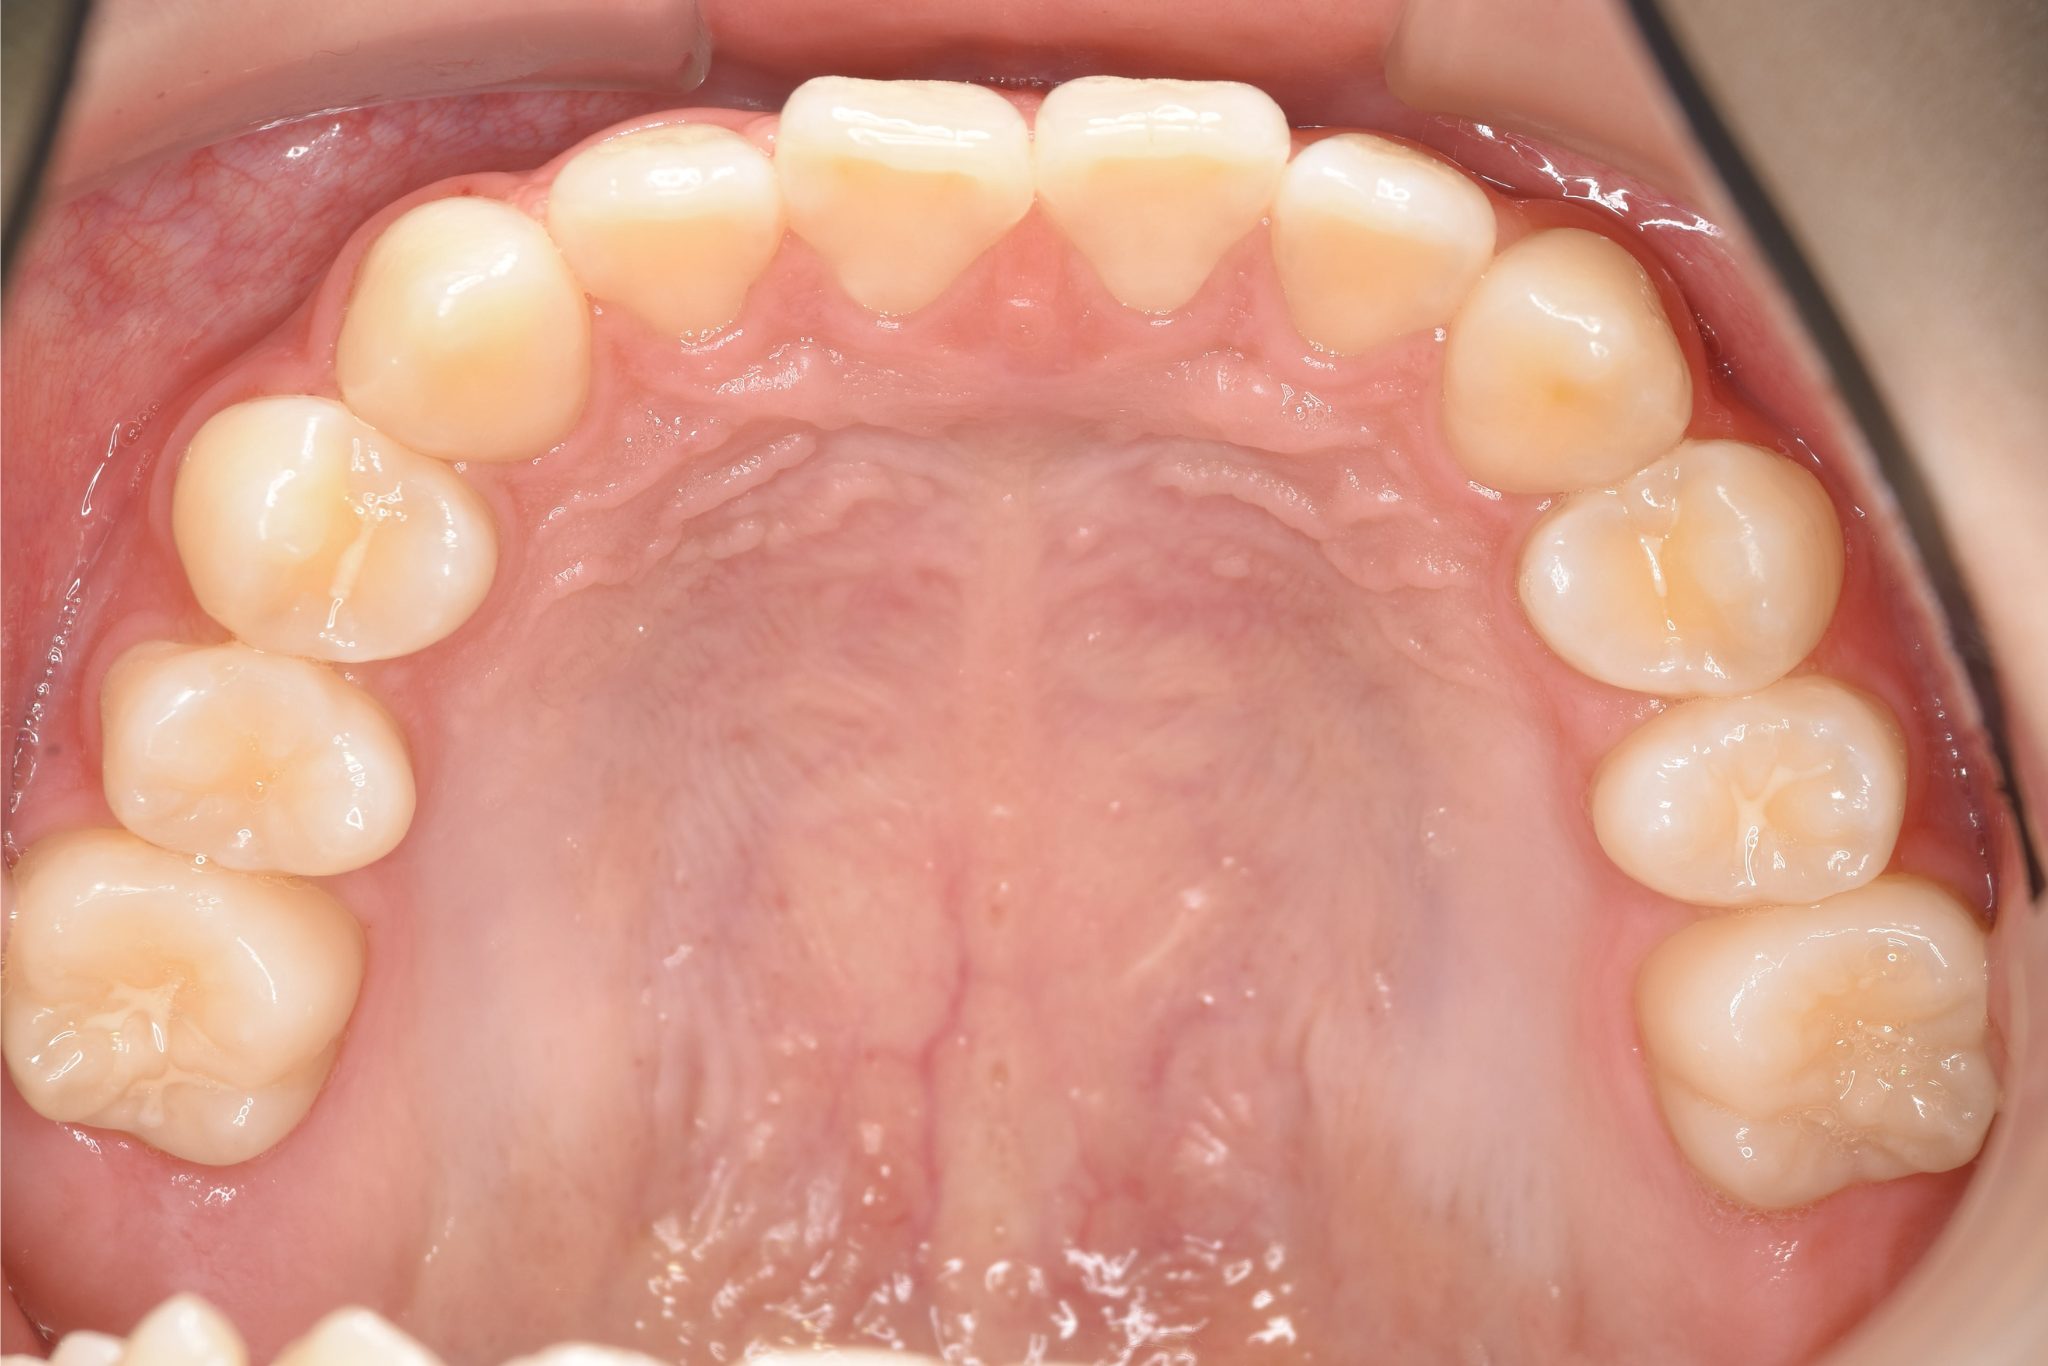

ビフォー

主訴 受け口

施術内容 上顎急速拡大装置と下顎リンガルアーチを用いて上下顎骨を拡大した。

上顎前方牽引装置を用いて上顎骨を前方に成長促進させた。

その後マウスピース型矯正装置で歯牙を配列し良好な咬合を獲得した。

治癒期間 2年9ヶ月間